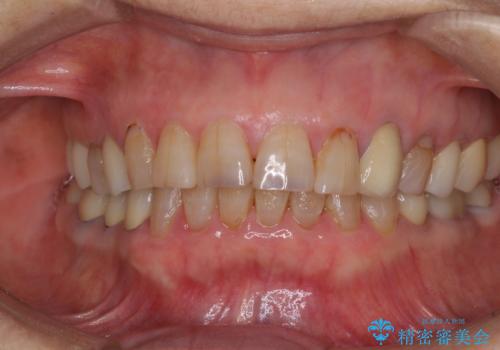

全ての奥歯の銀歯をセラミックに メタルフリー治療

途中体調を崩されてしまい、その間に仮歯が外れてしまうなど、治療期間が長引いてしまいました。

治療期間はかかってしまいましたが、念願のメタルフリーとなり、患者様には大変満足していただきました。